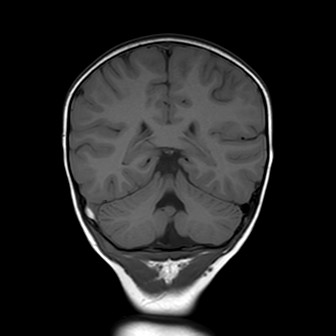

La bambina inizia quindi terapia con enoxaparina alla dose di 1700 UI x 2/die con aggiunta di terapia antibiotica con ampicillina-sulbactam per profilassi. Nei giorni successivi Teresa è stata bene, l’instabilità è andata progressivamente scomparendo senza vomito o cefalea. I successivi controlli all’angio-RM e alla TAC hanno mostrato un rallentamento del flusso in seno sigmoideo destro con tumefazione e netta iperdensità dello stesso, che sono andati progressivamente scomparendo con solo una minima falda ematica residua al giorno della dimissione, dieci giorni dopo il trauma. La terapia è stata dimezzata e poi interrotta dopo tre settimane dall’avvio.

La presenza di atassia alla marcia con vomito è un segno tipico della trombosi del seno sigmoideo che, per quanto rara nel bambino dopo un trauma, va esclusa con una angio-RM, non essendo la TAC in grado di visualizzare chiaramente il flusso nei seni venosi, soprattutto se all’immagine si sovrappone la contestuale presenza di un ematoma. Inoltre la progressione dei sintomi neurologici indicava il trattamento del trombo con eparina, a differenza dei casi asintomatici dove è indicata la semplice reidratazione per evitarne la progressione e lo sviluppo di ipertensione endocranica.